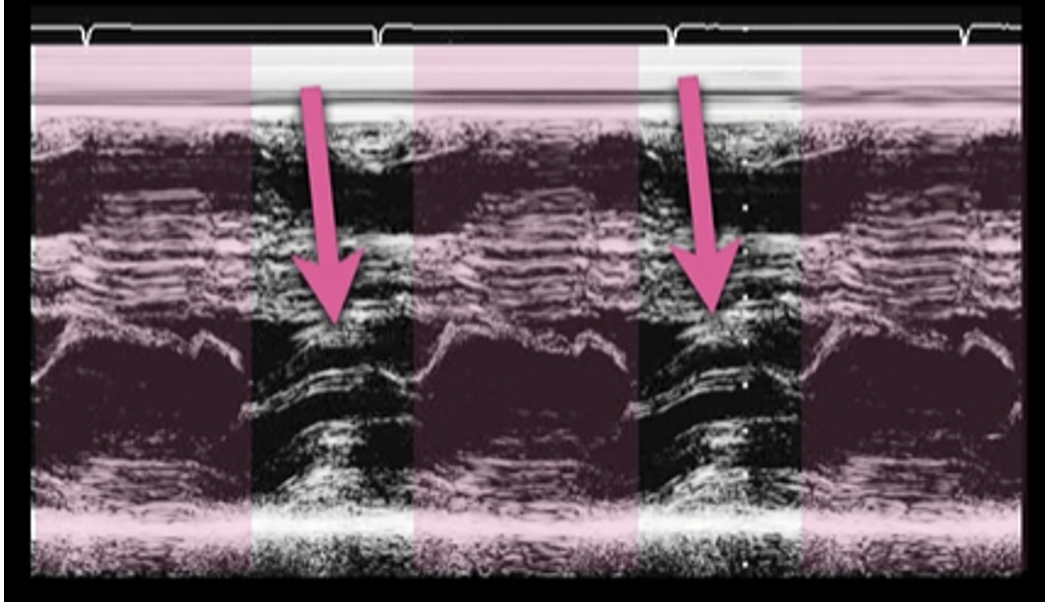

This is the M Mode on the PSL View of a heart with HCM. Notice how you see the opening of the mitral valve in diastole (valve touches the septum), BUT you see the mitral valve moving anterior during systole (arrows).

This is another example of SAM on a HCM patient.